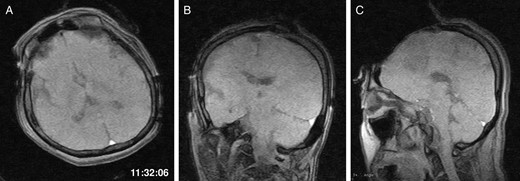

General anaesthesia was induced. Following left frontal craniotomy and dural incision, the first iMRI was performed (Fig. 1 ). One hundred fifty-eight minutes from induction, the patient regained consciousness after all anaesthetics were ceased. Tumour resection was performed with free conversation. However, after 143 min of surgery under the awake condition, the patient came to complain of excessive sleepiness though she could respond to verbal commands. Electrocorticogram (ECoG) did not detect after-discharge. The tumour was successfully removed en bloc fashion. Progressive brain swelling was not observed. The second iMRI was commenced 182 min into the awake phase (Fig. 2). Thirteen minutes from the beginning of the second iMRI scanning, the patient did not respond to noxious stimuli. When the patient was removed from the gantry, she was unconscious and had stopped spontaneous breathing. Her pupils were isocoria and did not dilate. Neither epileptic seizure nor anaphylactic reaction occurred. The peripheral oxygen saturation was not measurable, but cardiac instability or signs of vomiting were not observed. We decided to discontinue the operation under the awake status. No electrolyte imbalance or hypoglycaemia was observed. Subsequently performed iMRI identified a thin subdural haematoma in the contralateral side (Fig. 3). The fourth iMRI confirmed that most of the haematoma was evacuated following right frontal craniotomy.

The third intraoperative magnetic resonance images after intubation, axial (A), coronal (B) and sagittal (C) T1-weighted scout images show acute right-sided subdural hematoma (arrows), contralateral to the site of the craniotomy. The time of scan is superimposed.